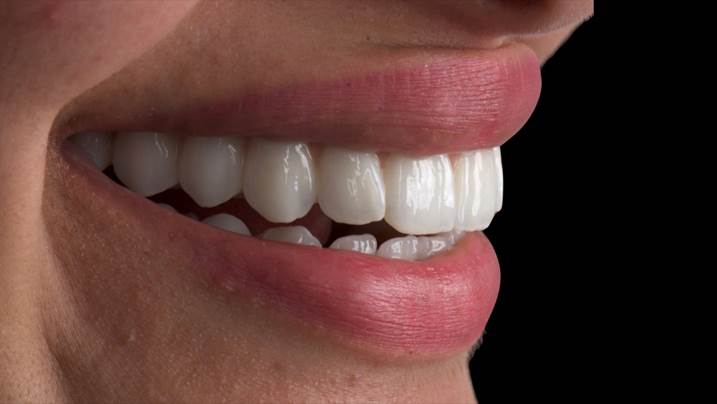

“AnyRidge shows excellent esthetic results

with Zirconia prosthesis in full-mouth rehabilitation case . ”

Clinical case: A Full transition from natural teeth to all-on-6 bridges

with AnyRidge implants